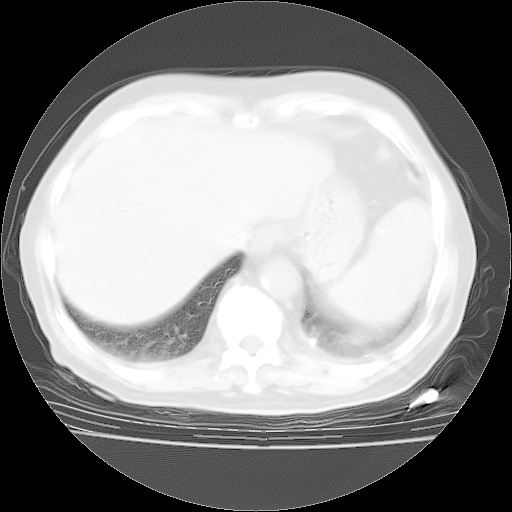

今天部分检查

轻微咳嗽,无痰,(体温正常时)R20次/分,P75次/分,双肺底、腋下可闻及少量捻发音。下肢轻度浮肿。

血常规:白细胞9.11×109/L,N0.92,L5.64,血小板39.2×109/L,HB148g/L,ESR2mm/H。

尿常规:潜血+

血生化:总蛋白69.71g/L,白蛋白38.40g/L,球蛋白31.31g/L,CRP27.9mg/L,尿素氮11.98mmol/L,肌酐106μmol/L,乳酸脱氢酶1099 U/L,肌酸激酶108U/L,CK-MB 61U/L。

腹部B超:胆囊壁增厚,肝、胆、胰、脾、肾无异常,肠系膜淋巴结、腹膜后淋巴结无增大。

ECG:右心室增大

心脏超声检查:无右心室增大。

增加治疗:异烟肼、利福平、乙胺丁醇,静滴左氧氟沙星、参麦注射液。甲强龙从80mg暂减为40mg。

强的松3月1日改为10mg qd,4月1日改为10mg qod。3月份以前的减量过程和环磷酰胺疗程需等明天查看记录(我岳父自己做的记录在他家里)。